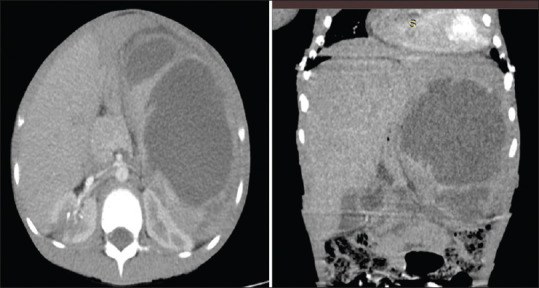

摘要:脾脓肿是一种危及生命的疾病,在儿童中非常罕见。患上脾脓肿通常有感染病灶或免疫缺陷等诱发因素。英文文献中仅报道过一例成人脾脓肿合并脑脓肿的病例。因此,我们报告了一例 11 岁男孩的病例,他原本身体健康,但出现发热和体重减轻 2 个月,右上腹痛、呕吐、下腹压痛 1 周,后来在就诊前 2 天出现左侧偏瘫和右侧面瘫。腹盆腔超声扫描、腹部和头颅计算机断层扫描证实了脾脓肿和右侧脑内脓肿的诊断。随后,他接受了经皮超声引导的脾脓肿引流术,但引流不成功,不得不进行脾切除术,并积极使用抗生素治疗。本报告旨在强调有必要加强对免疫力低下儿童脾脓肿的怀疑,并增加对这种罕见儿童疾病的管理知识。我们的结论是,脾脓肿并发脑内脓肿是一种罕见但危及生命的疾病,可通过脓肿引流和积极的抗菌治疗进行治疗。

Abstract: Splenic abscess is a life-threatening condition, which is very rare in children. There is usually an infective focus or pre-disposing factors such as immunodeficiencies towards developing splenic abscesses. Only one case of splenic abscess with brain abscesses in an adult has been reported in the English literature. We, therefore, report a case of an 11-year-old boy who was otherwise healthy, but presented with fever and weight loss for 2 months, right upper abdominal pain, vomiting, hypochondrial tenderness for 1 week and later on developed a left hemiplegia and right facioparesis 2 days before presentation. Diagnosis of splenic abscess and right intracerebral abscesses was confirmed with abdominopelvic ultrasound scan and abdominal and cranial computerised tomographic scans. He subsequently had percutaneous ultrasound-guided drainage of the splenic abscess which was not successful necessitating splenectomy with aggressive antibiotics treatment to which the patient responded with resolution of the brain abscesses and recovery of power in affected limbs. This report aimed to highlight the need for increased suspicion of splenic abscesses in children who are apparently immunocompetent and to add to the knowledge of management of this rare condition in children. We conclude that splenic abscess with intracerebral abscess is a rare but life-threatening condition which is amenable to treatment with drainage of abscess and aggressive guided antimicrobial therapy.